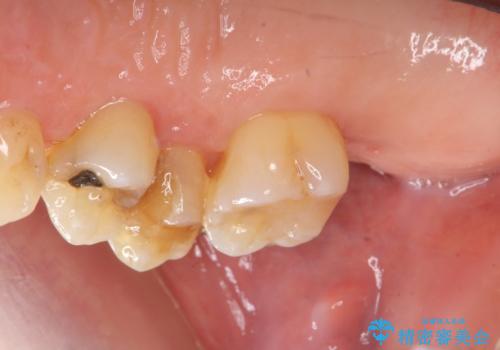

- 歯のぐらつき、歯周病の検査を希望され来院されました。

検査の結果、強い歯ぎしりによる歯の周囲の骨の吸収が認められたため歯槽骨の再生・歯周ポケットの除去・力に対抗する連結補綴・補綴前処置としての小矯正を計画します。